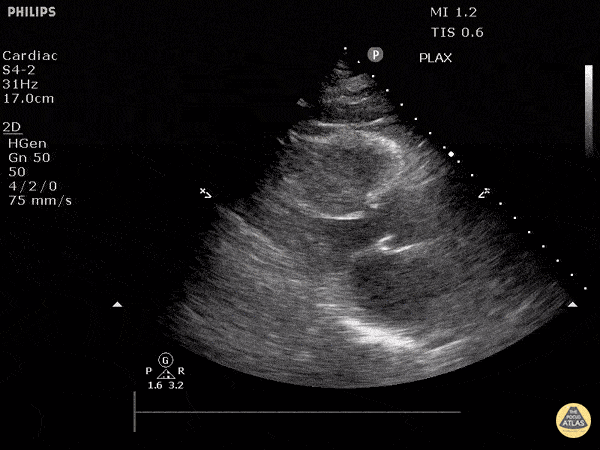

Parasternal uzun aks

Sol ventrikül fonksiyonunun değerlendirilmesi

Sol ventrikül (LV) fonksiyonu dört pencerenin tamamında değerlendirilebilir; ancak genellikle parasternal uzun aks görüntüsünde en kolay şekilde incelenir. Değerlendirme iki şekilde yapılabilir:

Görsel (subjektif) tahmin

EPSS (End Point Septal Separation) ölçümü

Çok sayıda çalışma, acil hekimleri ile kardiyologlar arasında global kardiyak fonksiyonun görsel değerlendirilmesi açısından yeterli uyum olduğunu göstermiştir.

RUSH muayenesinde genellikle ejeksiyon fraksiyonunun tam yüzdesine odaklanmak yerine, sol ventrikül fonksiyonunu geniş kategoriler halinde sınıflandırırız:

Hiperkinetik (hiperdinamik)

Normal

Azalmış (düşük)

Azalmış sol ventrikül fonksiyonunu düşündüren hızlı ve pratik bulgular şunlardır:

Sol ventrikül kavite çapının sistolde yaklaşık üçte bir oranında küçülmemesi

Miyokardın sistol sırasında yeterince kalınlaşmaması

Mitral kapağın ön yaprağının diyastolde septuma yaklaşmaması

Buna karşılık hiperdinamik bir kalpte, sistolün zirvesinde ventrikül duvarlarının neredeyse tamamen kollabe olup birbirine temas ettiği izlenir.